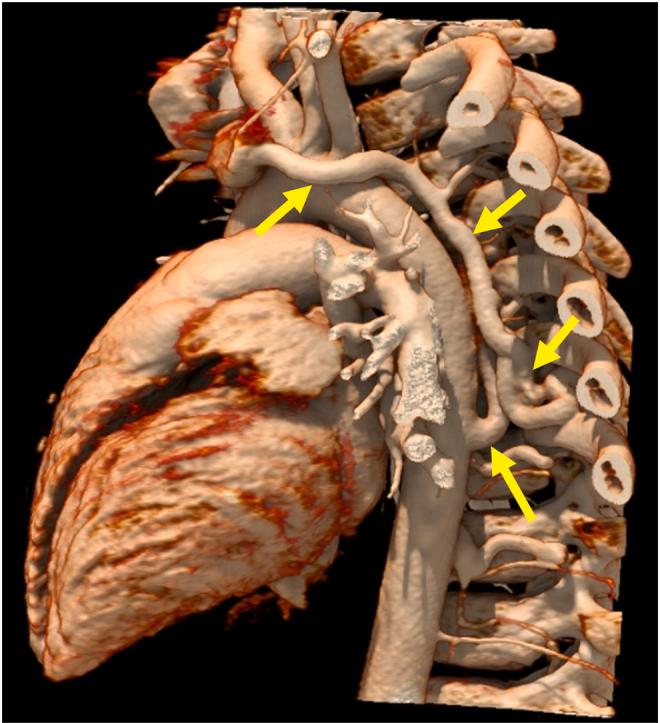

• Most AVFs present with a continuous murmur with radiation to the back. • There is little evidence to guide management of thoracic AVF. • Management options include surgical repair, embolization, or conservative management. • Conservative management is a reasonable approach in asymptomatic patients.